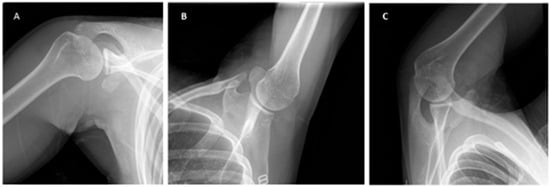

Figure 3. Off-track lesion on magnetic resonance imaging (MRI) arthrography. (A) In this case, the glenoid track is equal to 18.17 mm (27.1 – 5.2 × 0.83 = 18.17). (B) The Hill–Sachs index (HSI) is 22.1 mm (11.1 + 11). It is an off-track lesion because the glenoid track (18.17 mm) is less than the HSI (22.1 mm) [16].